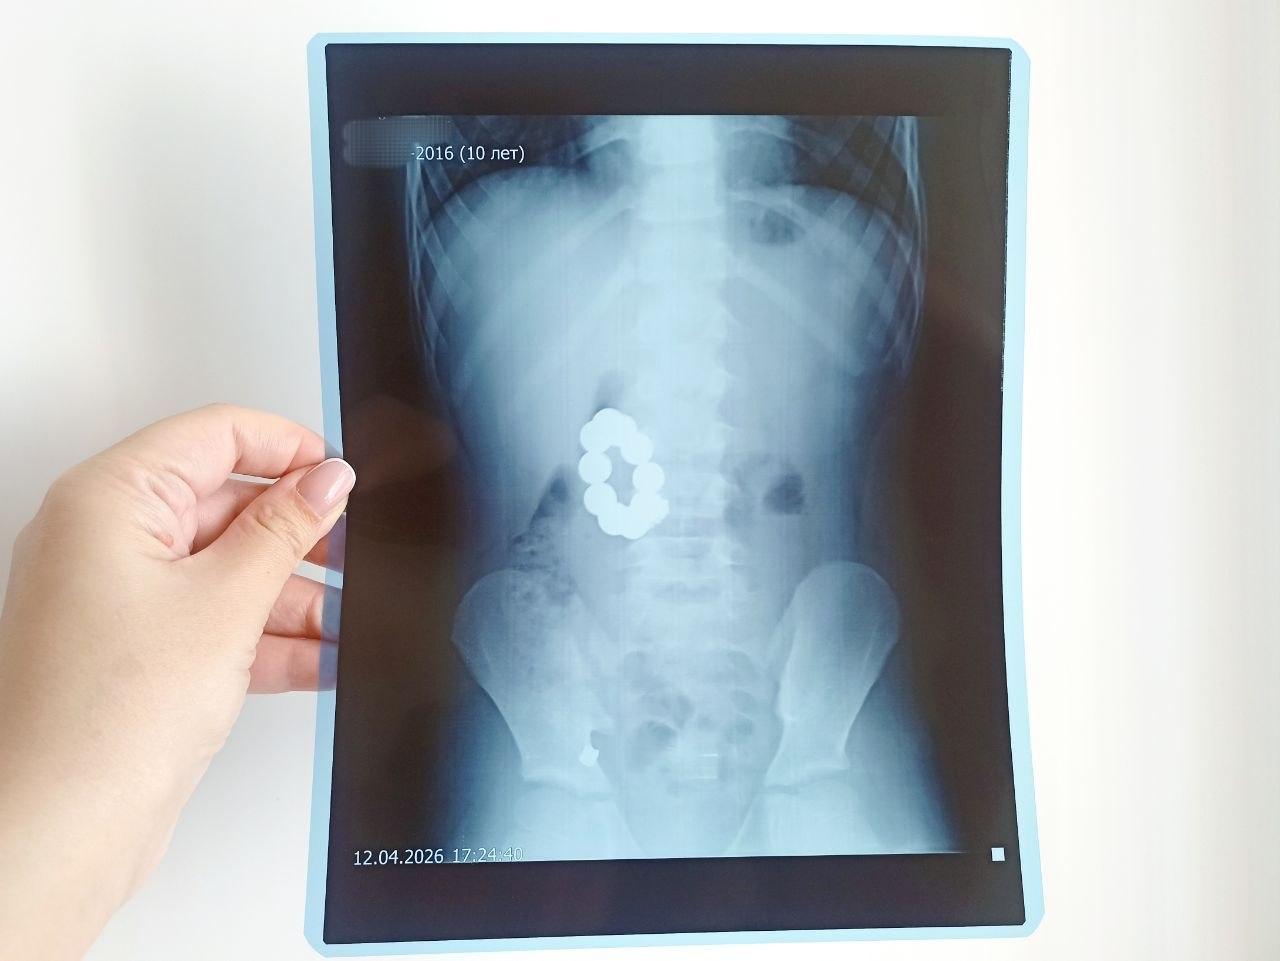

Диаметр каждого магнитного шарика составлял примерно один сантиметр

В Алтайском крае десятилетний школьник из села Волчно-Бурлинского Крутихинского района проглотил десять магнитных шариков диаметром около сантиметра каждый. Через два дня у него появились сильные боли в правой части живота и рвота.

Магниты соединились в области между желудком и двенадцатиперстной кишкой

Рентгеновское исследование показало, что магниты сцепились между желудком и двенадцатиперстной кишкой, а рядом находилась цепочка.